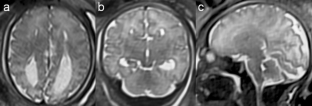

Fig. 4